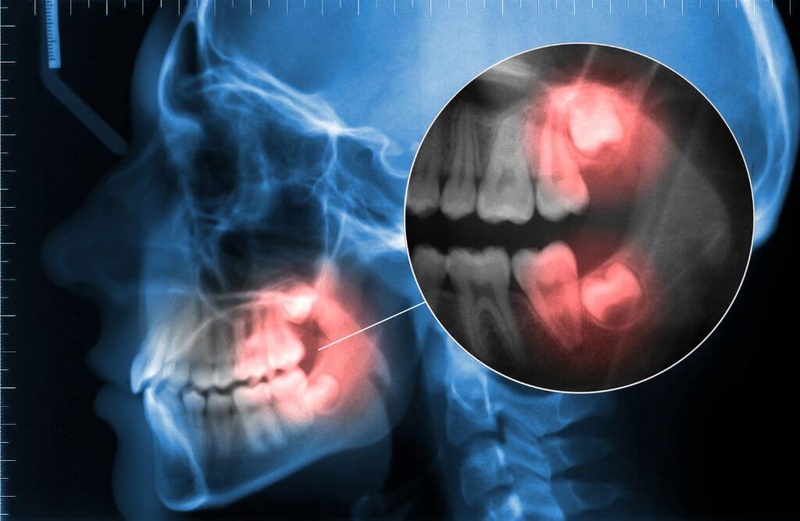

Răng khôn là chiếc răng hàm thứ 3, nằm cạnh răng số 7, sát vách hàm, thường mọc trong độ tuổi trưởng thành (17 – 25 tuổi).

Xương hàm của chúng ta thường chỉ đủ chỗ cho 28 răng vĩnh viễn. Vì thế, răng khôn thường không có đủ chỗ để mọc lên bình thường, dẫn đến hiện tượng mọc ngầm, lệch lạc, kẹt dưới lợi…

– Tổn thương răng bên cạnh: Răng khôn mọc ngầm, lệch có thể xâm lấn, xô đẩy, thậm chí là húc vào thân, chân răng bên cạnh. Trong trường hợp này, bác sĩ thường chỉ định nhổ răng khôn để bảo tồn răng bên cạnh.

– U nang xương hàm: Răng khôn mọc ngầm có thể gây u nang xương hàm, làm tổn thương răng, xương hàm, thậm chí là dây thần kinh.